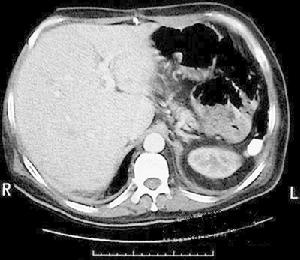

腦組織梗死液化(2)腦梗死:常起病突然,根據病情有穩定型和進展型之分,前者指病情穩定無進展,歷時24~72h又稱完全性腦卒中11%-13%患者起病隱匿無臨床症狀和體徵,僅影像學發現有缺血灶。

MRI(磁共振成像)MRI檢查對早期腦梗死的診斷有一定的幫助。發生腦梗死後6h梗死灶內水分已經增加3%~5%此時梗死灶呈長T1和長T2改變,表示存在細胞毒性腦水腫。在24h左右,梗死灶內血-腦脊液屏障破壞,注射Gd-DTPA做MR增強掃描可見明顯的信號增強發病1周后梗死灶仍可表現長T1和長T2,但T1值較早期縮短如梗死灶內有出血,呈T1值縮短而T2值仍然延長。